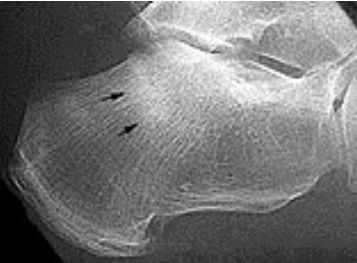

What do these images show? What is this disease called? How does this differ from Meuller Wiess Syndrome? | Osteochondrosis of the navicular. Kohler's disease. Kohler's disease only appears in children, Meuller Wiess Syndrome only appears in adults and is a spontaneus osteonecrosis of the navicular, not a true osteochondrosis. |